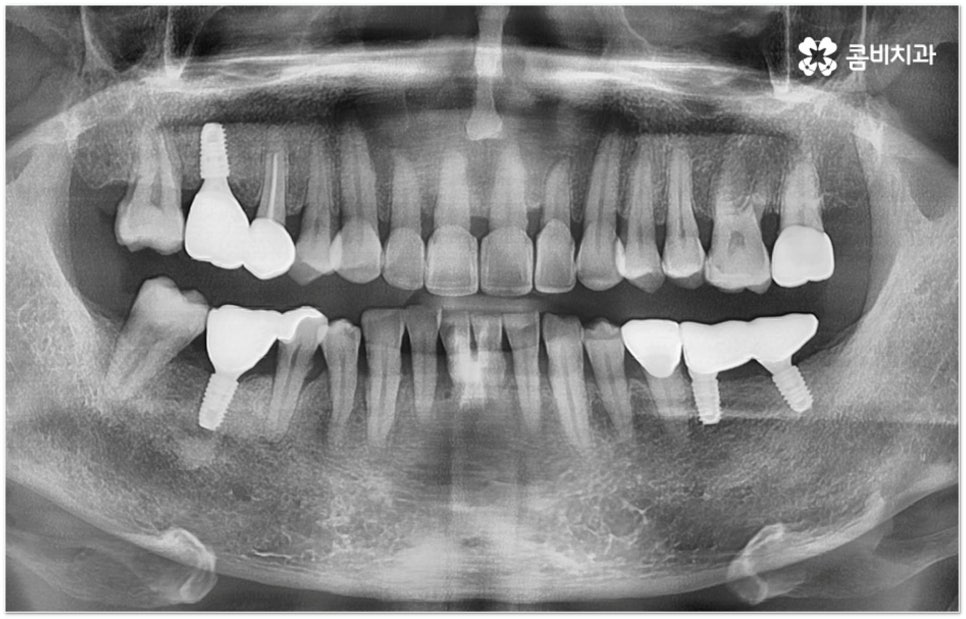

그러나 임플란트는 잇몸뼈에 직접 심어서 고정시키는 방식인 만큼 만약 환자분의 잇몸뼈가 부족하거나 치아가 빠진 후 오랜 시간이 지나 이미 잇몸뼈 소실이 상당 부분 이루어진 상태라고 한다면 먼저 골이식을 통해 이를 보충한 후 식립을 진행하는 뼈이식임플란트 방식을 이용할 필요가 있어요. 골이식 과정은 바탕이 되는 잇몸뼈의 밀도나 높이, 두께가 부족한 부분에 이식 재료를 심어주어 뼈를 재건해 주는 것인데 충분한 시간을 두고 무리하지 않게 진행하는 것이 뼈이식임플란트 수술의 성공률 및 안정적인 지속성을 높일 수 있는 방법이 될 거예요.

뼈이식임플란트 가 필요한지 살펴볼 때 3D CT 촬영과 같은 정밀 진단을 통해서 환자분의 잇몸뼈 두께 등 치조골 상태 뿐 만 아니라 구강 구조, 치아 및 잇몸 상태, 신경관 위치, 상악동까지의 거리 등을 꼼꼼하게 확인하여 치료 계획을 세우고 필요하다면 구강 질환에 대한 치료나 상악동 거상술 등을 선행하며 잇몸뼈 부족에 대해서도 골이식 과정을 먼저 진행하게 되는데요, 이러한 뼈이식임플란트 시술은 상당히 고난도의 복잡한 치과 진료인 만큼 관련 임상 경험이 풍부한 의료진과 함께 하는 것이 굉장히 중요하며 또한 수술 후 관리 면에서도 더욱 신경을 써 주시길 당부드리고 있어요.

특히 음주와 흡연은 염증 가능성을 높이고 치유 과정을 더디게 만들며 임플란트가 단단하게 자리잡는 것을 방해하므로 식립 실패의 대표적인 원인 중 하나라고 할 수 있는데요. 그렇기 때문에 최소 2주 정도는 술과 담배를 금하시는 것이 좋으며 이 밖에도 뼈이식임플란트 수술 후 치과에서 말씀드리는 주의 사항을 준수하고 꾸준한 검진을 통해 수술 주변 부위를 관리하면서 청결하게 유지할 수 있도록 노력하면 도움이 많이 될 거예요.